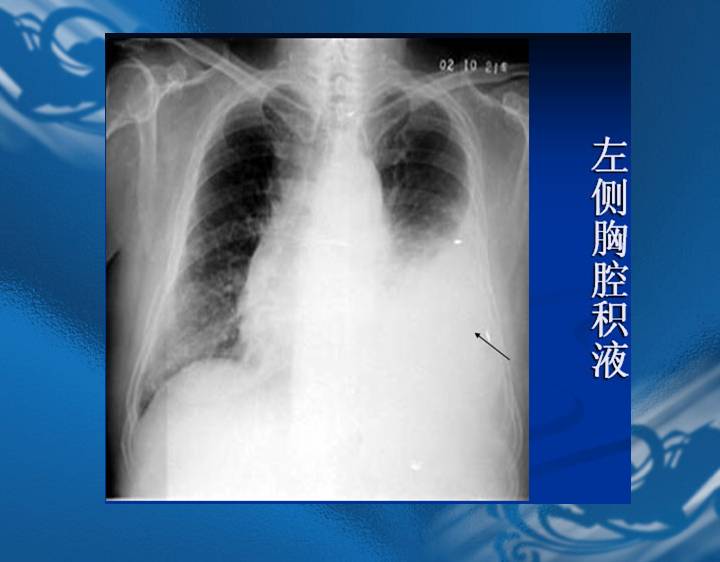

执业医师资格考试“实践技能”影像学辅导资料